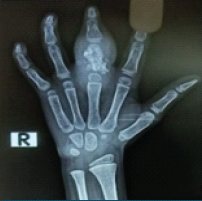

Reconstructive Surgery for Foot Ectrodactyly in an Adolescent Patient: A Case Report

Centenarro Jose S Meceda , Adrian Joseph C Tablante , Emiliano B Tablante ………………………………p.205-210